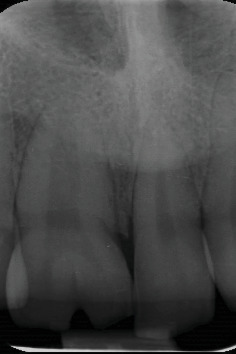

这个临床报告描述了一个18岁的男性患者,有新生和多余的上颌门牙导致前牙拥挤和审美问题。在这种情况下,保守的跨学科方法包括数字分析,多牙拔牙,正畸空间管理和陶瓷贴面。通过这些保守的多学科治疗和数字分析,保持了生牙的活力,美观,功能和患者自尊得到了显着改善。

This clinical report describes an 18-year-old male patient that had geminated and supernumerary maxillary incisor teeth causing anterior dental crowding and esthetic problems. In this case, a conservative interdisciplinary approach that included digital analysis, supernumerary tooth extraction, orthodontic space management, and ceramic veneers was done. With these conservative multidisciplinary treatments and digital analysis, the vitality of the geminated tooth was maintained, and the esthetic, function, and patient self-esteem were improved significantly.